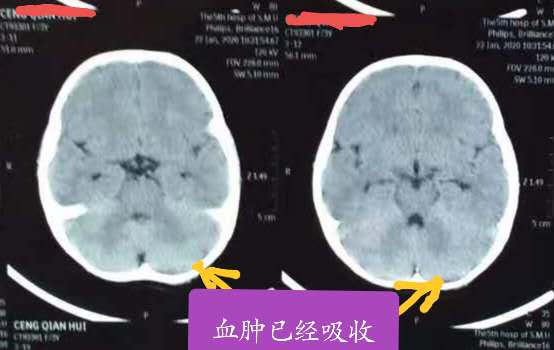

治疗后血肿吸收

3岁小孩,玩耍时跌倒头枕部着地受伤,致头疼不适,送去某医院求治,CT检查发现:左枕及小脑硬膜外血肿(图1-2)。该医院医生意见:开颅手术清除血肿。理论上讲,确实有手术指征!但是这个病人家属担心开颅手术风险太大,对小孩影响不好,拒绝手术。后来经过中西医结合保守治疗(20天左右),逐渐好转并完全治愈(图3-4)。有时候病人的治疗需要根据病情综合考虑,如果没有慎重考虑,匆忙做了手术,可能符合治疗原则,但是给病人带来了不必要的痛苦,增加了病人的经济负担和心理创伤!当然这更需要医生的诊疗技术、责任心和担当![加油][加油][加油]